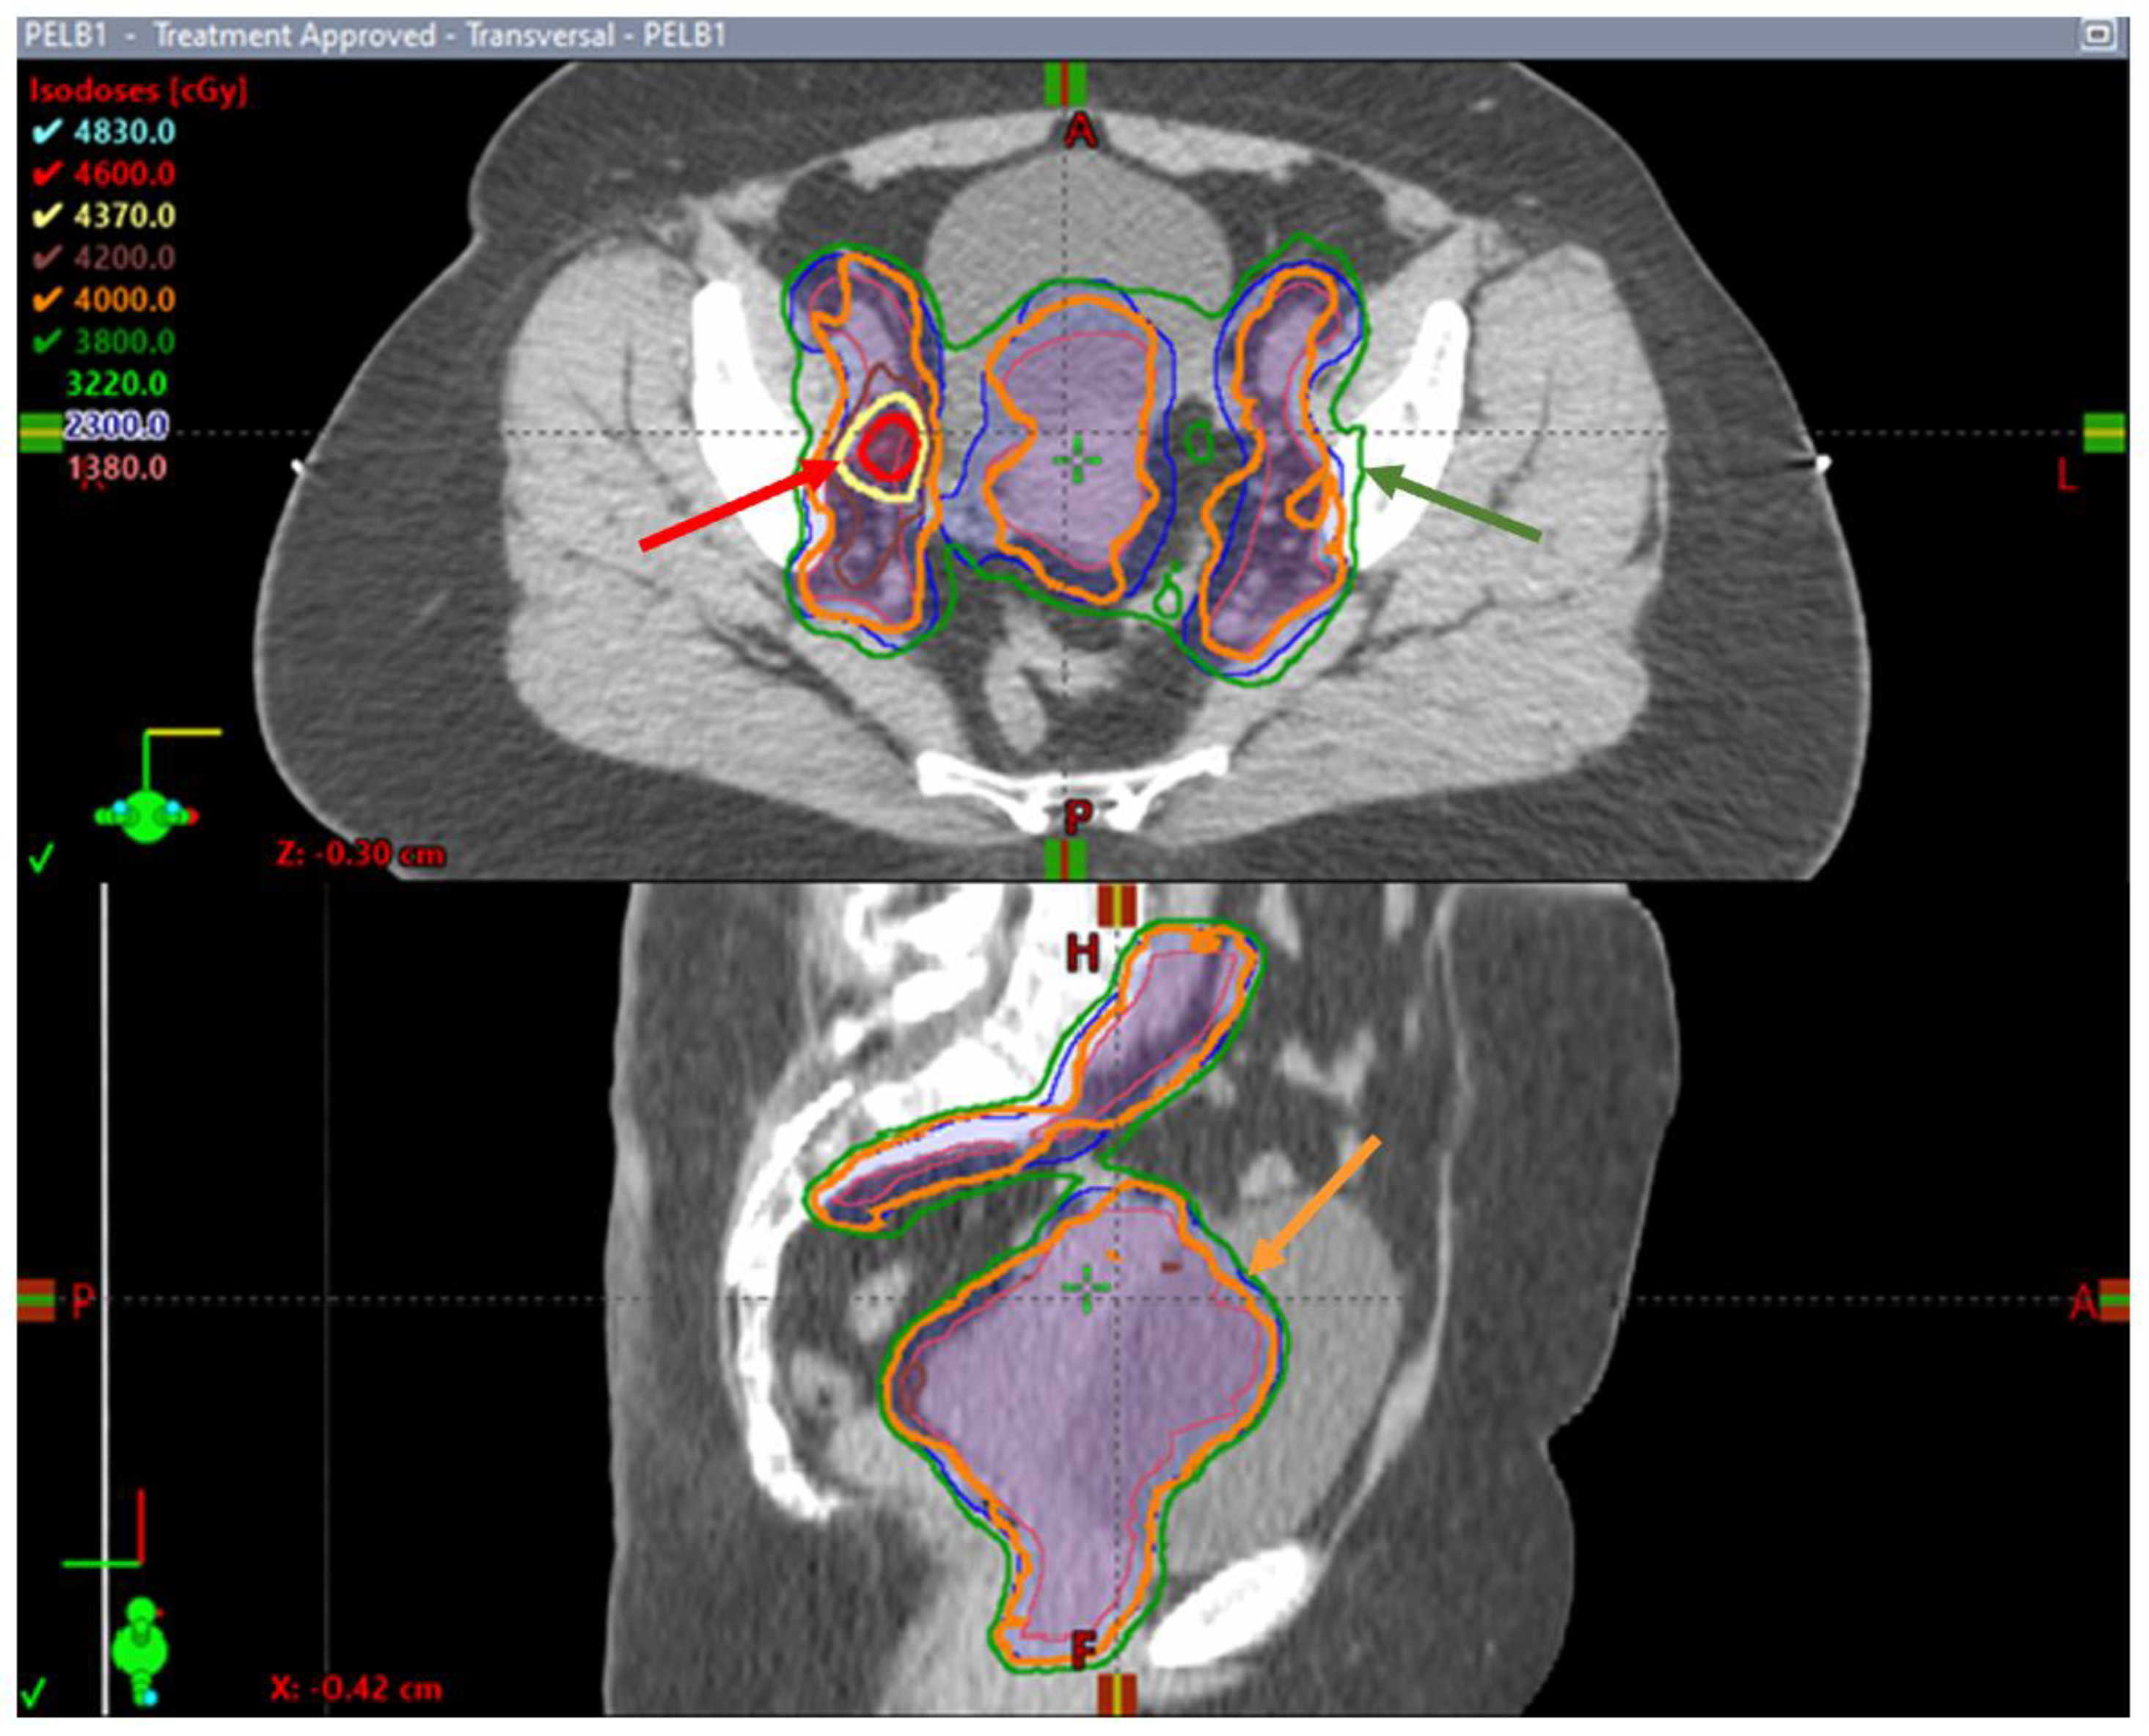

- Leung, E.; Gladwish, A.P.; Davidson, M.; Taggar, A.; Velker, V.; Barnes, E.; Mendez, L.; Donovan, E.; Gien, L.T.; Covens, A.; et al. Quality-of-Life Outcomes and Toxic Effects Among Patients with Cancers of the Uterus Treated with Stereotactic Pelvic Adjuvant Radiation Therapy: The SPARTACUS Phase 1/2 Nonrandomized Controlled Trial. JAMA Oncol. 2022, 8, 853. [Google Scholar] [CrossRef] [PubMed]